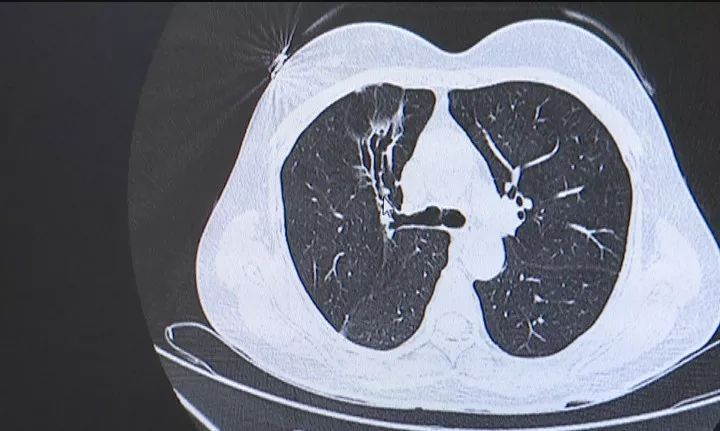

醫(yī)生表示,梅女士的情況有兩個(gè)原因,一個(gè)是她本身有支氣管擴(kuò)張的疾病,另一個(gè)是在這個(gè)基礎(chǔ)上合并了一個(gè)細(xì)菌感染,造成了咳血的情況。

讓人沒(méi)想到的是,經(jīng)過(guò)檢測(cè),梅女士所感染的細(xì)菌來(lái)頭可真不小,是一種罕見(jiàn)的致命性真菌尖端賽多孢菌。它多寄生于腐敗生物中,肺移植和免疫力缺陷的人才會(huì)感染,像梅女士這樣免疫力正常的人群,感染此類真菌極其罕見(jiàn)。這下就讓梅女士有些二丈和尚摸不到頭腦了。

但是,使用營(yíng)養(yǎng)土的人有那么多,怎么偏偏就是梅女士被感染了呢?醫(yī)生表示,是因?yàn)槊放孔陨碛幸粋(gè)結(jié)構(gòu)性肺病,給真菌造成了一個(gè)滋生的環(huán)境,在其抵抗力差,比較勞累的時(shí)候,便造成了她的發(fā)病。